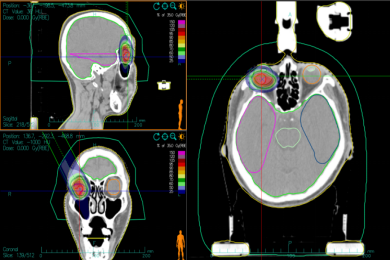

Case 3: Female, 59 years old, postoperative right orbital ACC. She underwent ‘right orbital mass excision + orbital repair’ at West China Hospital of Sichuan University in April 2023, and her postoperative examination showed that she had ACC. she was admitted to our hospital one month after the operation, and now she has obvious limitations in eyelid closure, right eye external rotation and downward rotation. After a thorough examination and evaluation of the patient, the patient was treated with CIRT on 12 June 2023, with one prescribed dose of PTVboost: 15Gy (RBE)/5fx. the second prescribed dose was PTV: 54Gy (RBE)/18fx, and the total tumour dose amounted to 69Gy (RBE)/23fx, with the dose distribution shown in Fig. 7. the CIRT and VMAT plans, under the premise that both meet the prescription requirements, the typical comparison of dose distribution in axial images, the surrounding normal tissue CIRT plan is significantly smaller than the VMAT plan low-dose irradiation range, see Figure 8.The efficacy of CIRT treatment was compared by imaging data before and after treatment, and the patient's efficacy was assessed according to the RECIST1.1 criteria for evaluating the effectiveness of tumour efficacy, which reached a partial remission (PR), see Figure 9. During CIRT treatment and within 1 month after treatment, the patient experienced grade 1 radioskin injury, and no adverse events greater than grade 2 were observed. As of July 2024, the patient is currently surviving with tumour and continues to be followed up in the long term.

Figure 7 Ion therapy dose distribution in orbital ACC patients

Note: Figure 7A: One course CIRT dose distribution. Figure 7B: Two course CIRT dose distribution

Figure 8 VMAT plan and carbon ion plan dose distribution in orbital ACC patients

Note: Figure 8A: VMAT plan dose distribution n orbital ACC patients. Figure 8B: Carbon ion plan dose distribution n orbital ACC patients.